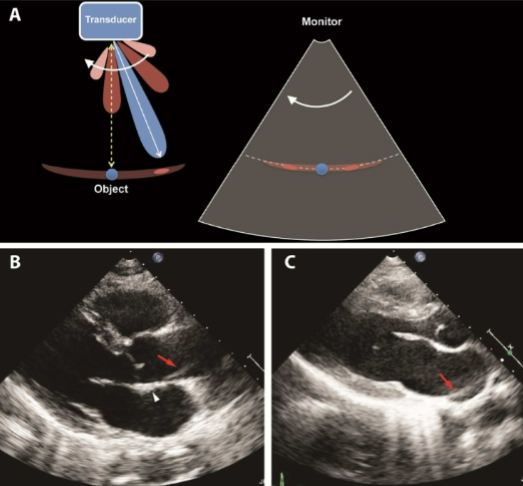

Slice (Section) Thickness

AKA Partial Volume Filling

Beam is too thick in the elevation plane

Gives the appearance of debris in an echo-free structure

Partial Volume Filling, thick, elevational, echo-free

Slice (Section) Thickness Artifact

AKA ___ ___ ___

Beam is too ___ in the ___ plane

Gives the appearance of debris in an ___ structure